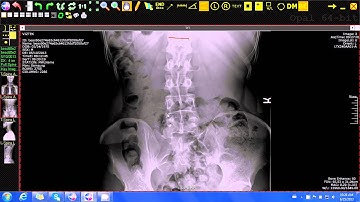

20 Multiple Cobb Angles Tool